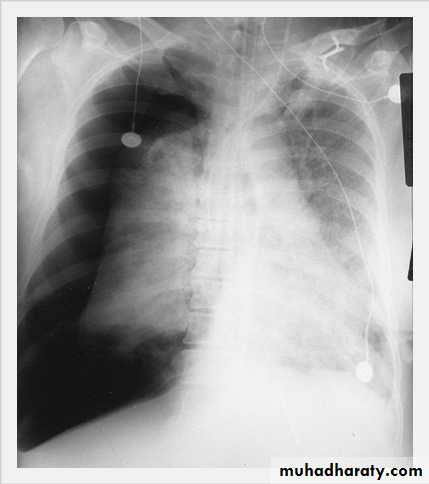

Massive pleural effusion with mediastinal shift to the left.

(A) Chest radiograph

(B) CT coronal reconstruction. A massive effusion displaces the mediastinum to the left. CT shows the important pleural effusion together with the enhanced atelectatic left lung.

Note also the depression of the right hemidiaphragm (arrows).